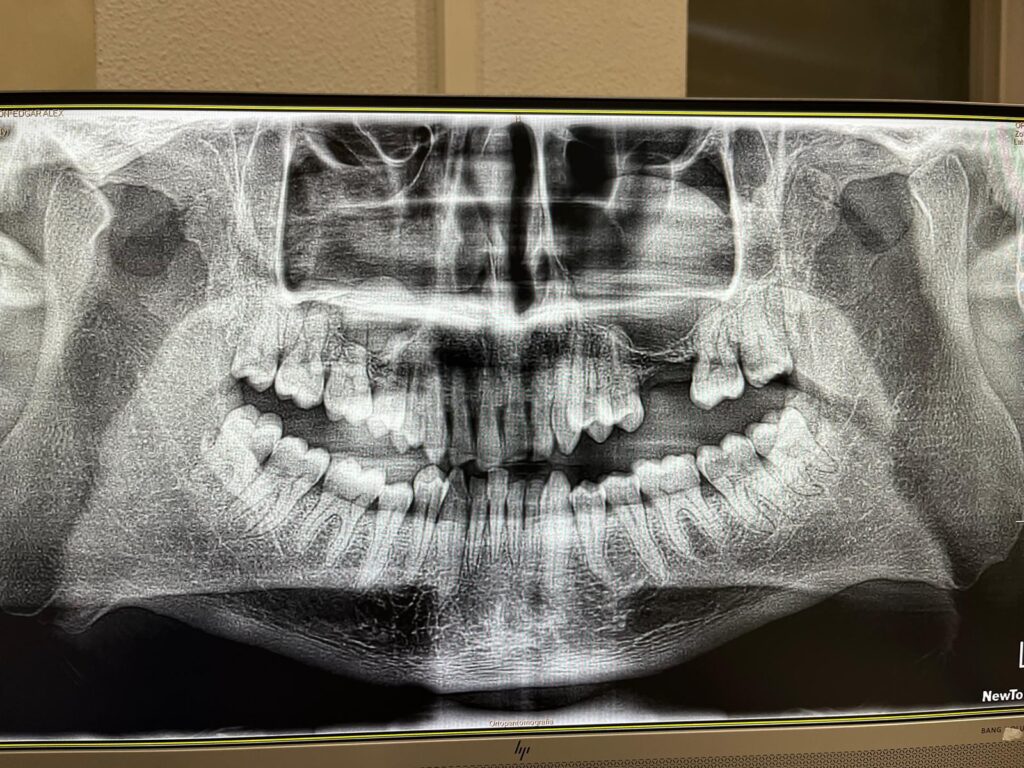

Cada paciente que llega a AVR inicia su tratamiento con un plan completamente personalizado. Nos tomamos el tiempo para evaluar en detalle las necesidades específicas, realizar estudios precisos y diseñar la solución ideal. En este caso reciente, la planificación con imágenes 3D fue crucial para definir la ubicación exacta de cada implante y garantizar un resultado estructuralmente sólido y estéticamente impecable.